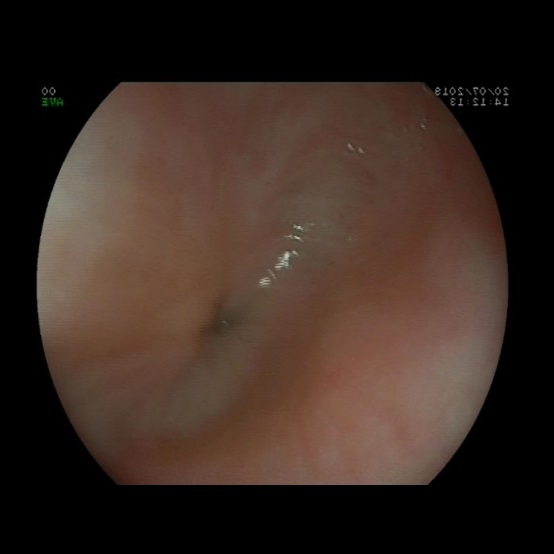

Como parte del estudio se realiza un estudio analítico y una ecografía abdominal, que no muestran alteraciones. Dada la persistencia del cuadro de vómitos, se decide realizar una endoscopia digestiva alta ( Fig. 1) en la que se evidencia una estenosis esofágica que impide el paso del endoscopio. El tercio proximal del esófago se muestra dilatado, sin estrías ni anillos. Se completa estudio con tránsito digestivo superior ( Fig. 2), donde se confirma estenosis esofágica en el tercio medio-distal, con escaso paso del contraste. En la anatomía patológica de la mucosa se observan cambios inflamatorios de características inespecíficas, sin metaplasia intestinal.

La endoscopia suele mostrar un estrechamiento concéntrico, sin alteraciones macroscópicas en la mucosa 4. La histología de la mucosa también debe ser normal, sin datos de reflujo, esofagitis péptica o esofagitis eosinofílica. Por este motivo, esta entidad debe ser sospechada siempre que exista una estenosis con visualización de una mucosa normal 4.